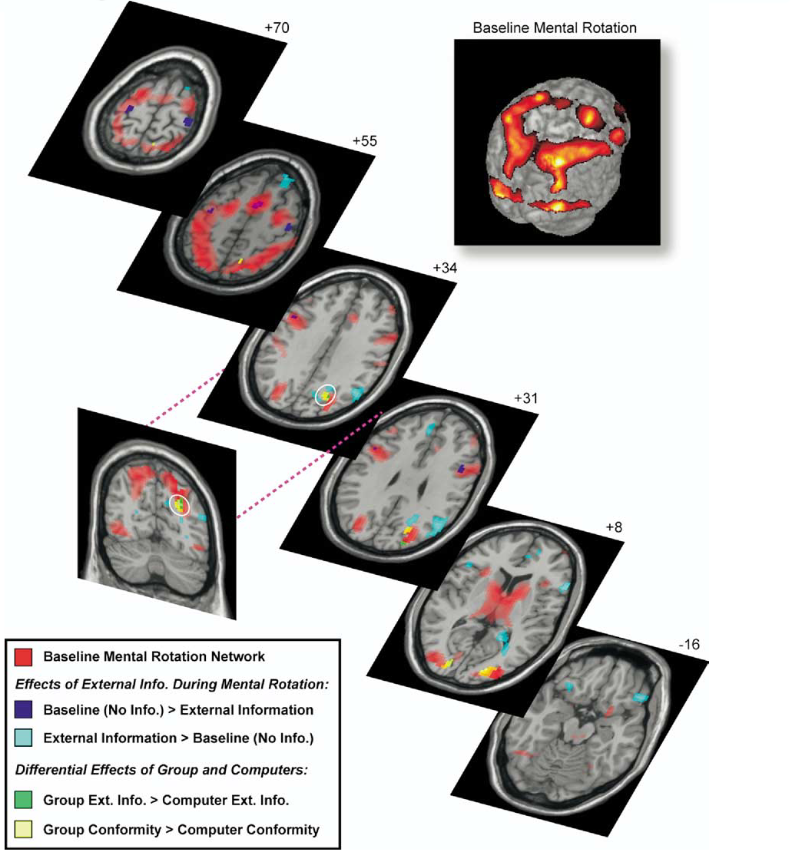

Os indivíduos (PEF) podem capitular relativamente à pressão do grupo (Classe de PEF), não como uma parte de um contrato social, mas devido ao desconforto (desagradável) de assumir uma posição individual (isolamento), assumindo a opinião da maioria como mais apelativa que as crenças pessoais para evitar o desconforto da crítica. Gregory Berns e colaboradores investigaram, recorrendo à tecnologia da Imagem Funcional da Ressonância Magnética (fMRI), o problema da “Conformidade Social” que é um forte entrave à mudança de crenças, investigação essa que podemos utilizar para compreender o comportamento dos Professores de Educação Física. A modificação do julgamento (perceção) quando está sob a pressão do grupo, foi inicialmente demonstrada num conjunto de experiências desenvolvidas por Solomon Asch (1951-1952).

A conformidade foi definida como a concordância com fontes exógenas de informação, sejam pares ou computadores, quando a informação estava errada. A conformidade corresponde ao comportamento mensurável através da mudança na taxa de erros dos participantes entre a sua performance de base e as condições através das quais a informação era apresentada. A taxa de erro aumentou até 41% quando o grupo veiculou informação errada, a qual foi significativamente maior que a informação errada partilhada pelo computador (média 32%).

- A conformidade – dependência foi definida como as tentativas nas quais o participante concordou com a informação externa quando esta estava incorreta.

- A não-conformidade – independência foi definida como as tentativas na qual o participante deu a resposta correta quando a informação externa estava incorreta.

O Próprio Asch levantou a questão sobre a possibilidade da pressão social alterar a perceção. Estudos anteriores mostraram que a atividade nos neurónios do córtex visual apresentam uma maior correlação com a perceção do que com as propriedades dos estímulos.

A dor da independência:

Comparativamente à investigação comportamental sobre a conformidade, pouco se sabe sobre os mecanismos da não-conformidade ou independência. Dependendo da situação em particular, a influência do grupo pode ser puramente informal – fornecendo informação ao indivíduo que se mostra inseguro relativamente ao que fazer. Mais interessante é o caso onde o indivíduo manifesta opiniões definidas sobre o que fazer mas conforma-se devido a uma influência normativa do grupo por razões sociais (obrigação profissional imposta pelos normativos legais). Neste modelo, presume-se que as influencias normativas atuem através da aversão de estar na posição da minoria. A ativação da amígdala nesta investigação torna-se num marcador claro da carga emocional associada com o facto do sujeito assumir (fazer frente) e defender as suas próprias crenças. A ativação da amígdala tem sido associada frequentemente com estados emocionais negativos mas também se sabe que a amígdala modula o comportamento social e é ativada pelos rostos humanos, sobretudo quando estes assumem uma importância emocional.

O responsável por esta investigação, o neurocientista Gregory Berns cit. Philip Zimbardo (2007) concluindo que “Nós gostamos de pensar que ver é acreditar, mas os resultados do estudo mostram que ver é acreditar naquilo que o grupo nos diz para acreditar”. Isto significa que a perspetiva das outras pessoas, quando cristalizada no consenso do grupo, pode na verdade afetar a forma como percebemos aspetos importantes do mundo exterior, fazendo-nos questionar a natureza da verdade em si. “Só quando nos tornarmos conscientes da nossa vulnerabilidade à pressão social então poderemos começar a criar resistência à conformidade, quando não é do nosso melhor interesse cedermos ou rendermo-nos à mentalidade dominante do rebanho”, Philip Zimbardo (2007).

- Gregory S. Berns et al. Neurobiological Correlates of Social Conformity and Independence During Mental Rotation. Biol. Psychiatry 2005;58:245–253: PDF